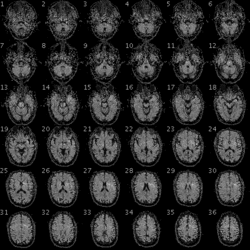

L'enregistrement du signal demande une coopération du patient, généralement dans le but d'alterner des périodes d'activité cérébrales (par exemple bouger les doigts de la main droite) avec des périodes de repos. Pendant ce temps sont acquises des images de l'intégralité du cerveau toutes les 1,5 à 6 secondes (correspond à la résolution temporelle moyenne classiquement utilisée en recherche). Au cours de l'examen, le patient doit réaliser des tâches selon des consignes précises expliquées avant l'examen. Par exemple, il doit faire un mouvement de la main droite pendant 20 secondes toutes les 50 secondes, ou bien il doit trouver des mots commençant par la lettre désignée par la consigne ; pour cela un signal lui est donné pendant l'acquisition des images soit par un écran soit par un casque audio.